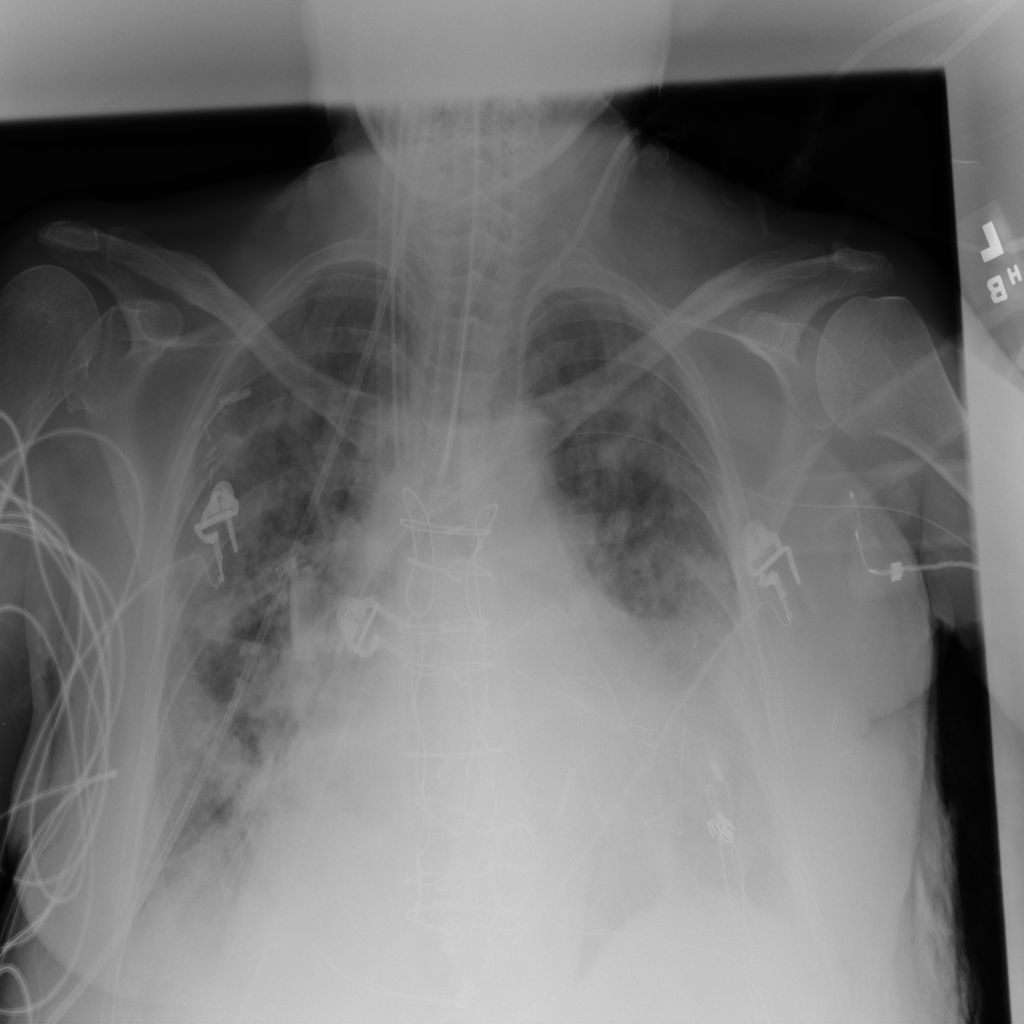

PAT-3384 · IMG-021Cardiomegaly

PAT-3384 · IMG-021

AP